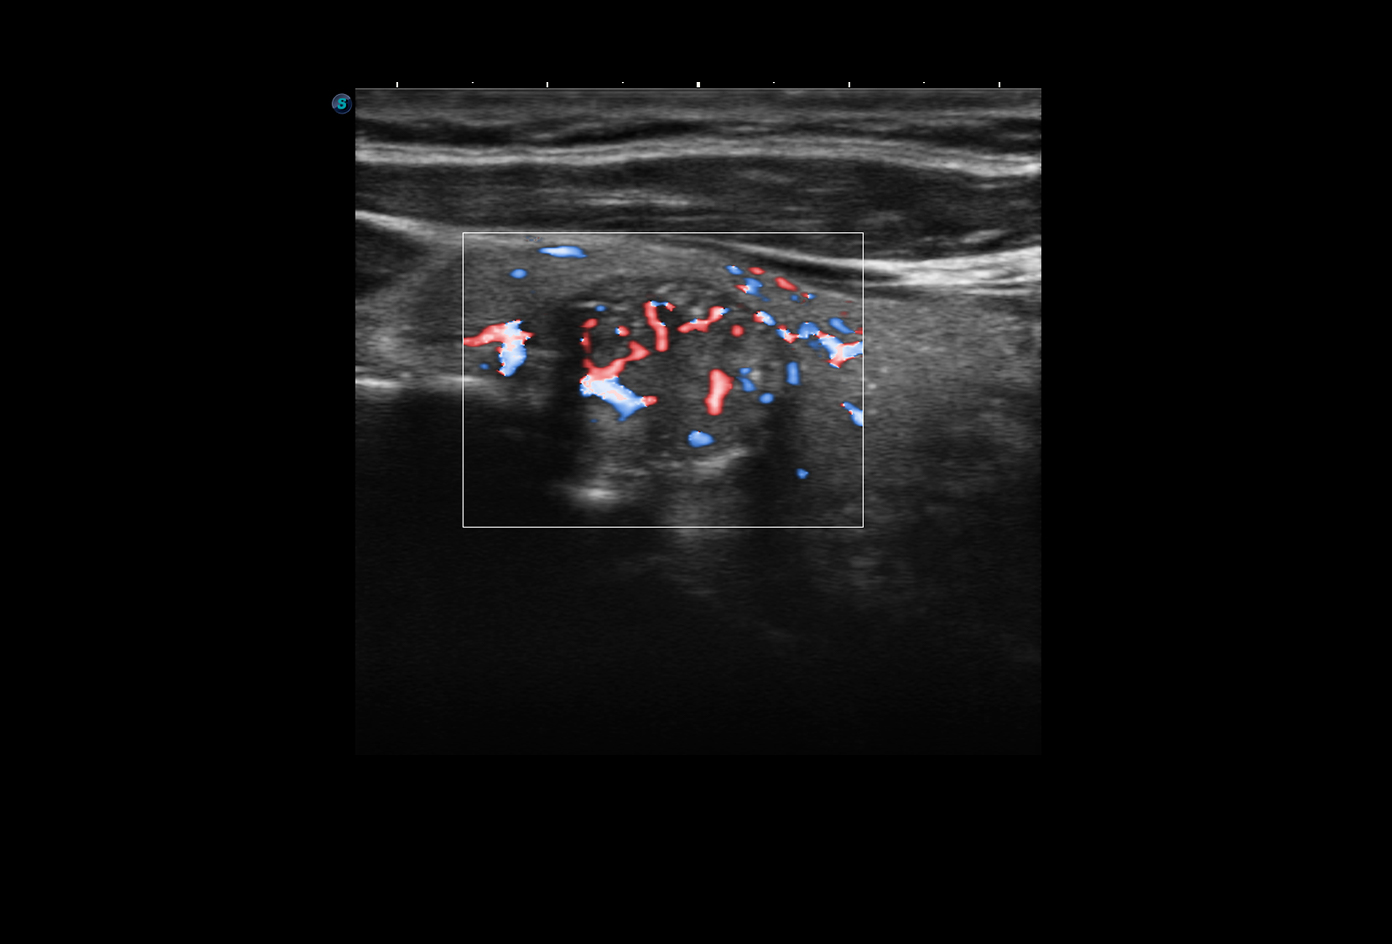

- Chế độ Doppler màu (CFM, PDI/DPDI): giúp đánh giá lưu lượng máu qua tim và mạch máu.

Hình ảnh siêu âm Doppler thận sắc nét